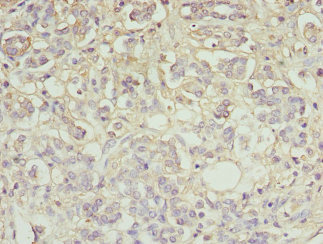

圖片:

應(yīng)用范圍:ELISA, IHC

Application Recommended Dilution IHC 1:20-1:200 -